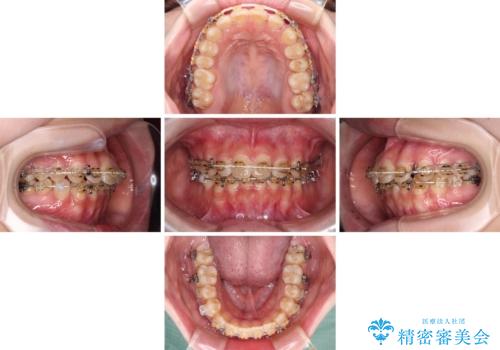

- 大学病院にて装置を装着したものの、治療が十分に受けることができないとのことで転院をされた患者様です。

上顎歯列が前方にあり、口元が閉じにくくなっていたため、既に装着されている装置を使用して上顎歯列全体を後方に移動させていくこととしました。

舌の突出癖があり、それが原因で上下前歯に隙間ができていたため、改善のためのトレーニングを行うように指示をしました。

舌の突出癖の影響か、なかなかスペースが閉じきらず、治療期間は予定よりも長期間となりました。

舌突出癖改善のトレーニングの重要性を認識することとなりました。